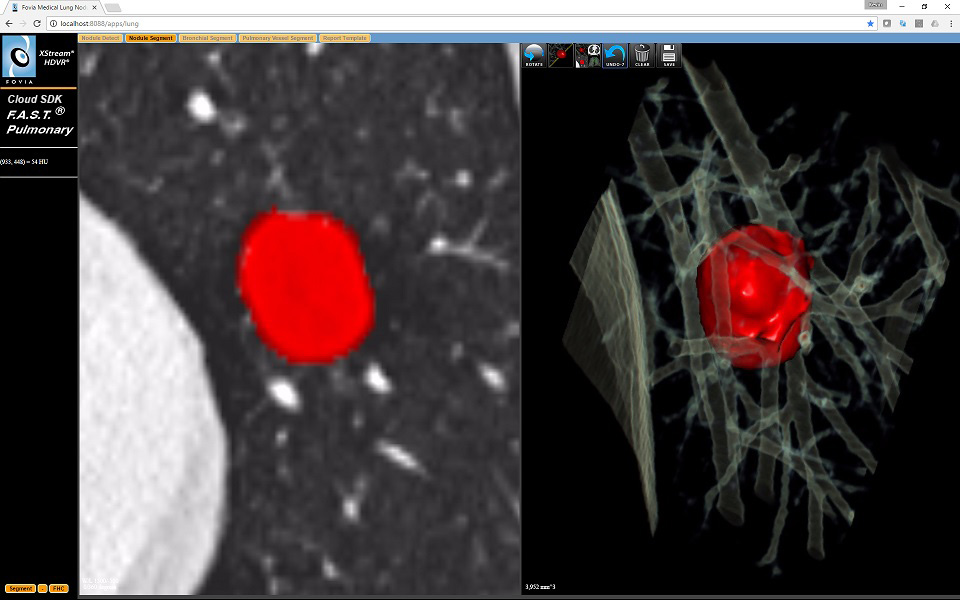

The Nodule Segment Tab of the application consists of 2

viewports

Left – Oblique MPR centered on the Nodule Detect Click

Point. Rotating spins this oblique viewport around the vertical

axis. Segmenting of the nodule is easiest achieved from this view.

Alt-left click and start by moving the mouse up and to the right, to

segment more of hte nodule. From there adjust the mouse to get the

object you wish (vertical movemetns adjusts the size of the growable

object, horizintal movement expands or decreases the density reange of

what wil be segmented) before letting the mouse button up.

Right – 3D SubCube which will rotate about the Nodule Detect

Click Point. It show the Interactive Segmentation and allows Free Hand

Cut to clean up segmentation errors. Undo and Clear All buttons are

present. Also a button to save the current segmentatoin info as a

"finding" for the Report Tab

The Nodule Segment Tab of the application consists of 2 viewports